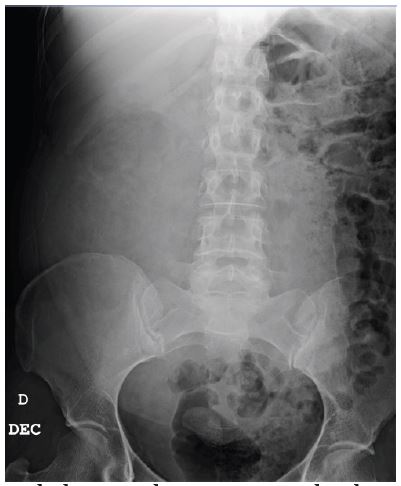

Patient A presented to the Emergency department with two episodes of presyncope, which were subsequently associated with intense abdominal pain. An abdominal tumor was palpated. The abdominal x-ray showed a large mass that had displaced the bowel (Figure 1). CT findings compatible with Wunderlich syndrome were additionally observed in patient A, although there was no evidence of active bleeding (Figure 2). Given the size of the lesion and the high risk of bleeding in this patient, an open partial nephrectomy was performed. A midline laparotomy revealed a large mass that was excised under arterial clamping with a total ischemia time of eight minutes (Figure 3). The weight of the surgical specimen was 2480 grams (Figure 4). The surgical procedure lasted 3 hours and we transferred and two units of red blood cells were subsequently transfused. On the 8th day, peritoneal drainage was removed, and patient was discharged.

Figure 1: The abdominal x-ray reveals the displacement of the bowel loops into the left hemiabdomen.